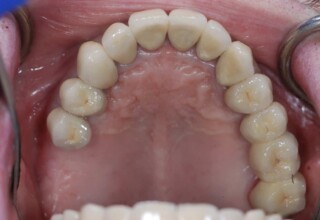

Full mouth prosthetic reconstruction on implants with a different approach on upper and lower jaw

Lower jaw: extractions, direct implant placement and immediate loading (same day) with a transitional bridge.

Upper jaw: Sequential extractions, sequential implant placement and gradual incorporation in the temporary bridge so that the patient was never left without fixed teeth. The aim of the above approach was to have the patient in continuous functional and aesthetic reconstruction, without immediate loading due to anatomical restrictions. Old smiling photos of the patient were used because the natural shape of the teeth was completely lost due to repetitive prosthetic attempts. Tooth relationship and teeth-lip support was transferred to the temporary restorations. Two different transitional bridges were needed to fully estimate phonetics, mastication and esthetics. After the necessary adjustments were finalized, the temporary bridge was used as a guide for the permanent bridges.

Initial

Intermediate

Final